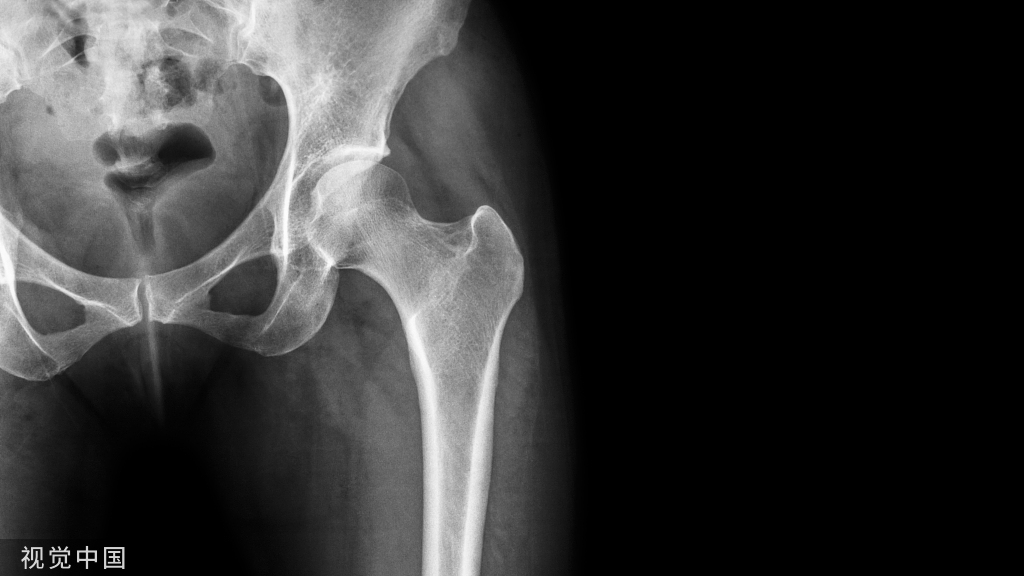

肘关节是连接上臂和前臂的铰链关节。在肘部,许多解剖结构允许明显的活动以实现屈曲和伸展功能,促进前臂旋后和旋前,并允许手腕和手的运动。由于肘部肿瘤的复杂性,肘部肿瘤的切除是一项重大的挑战,需要仔细的术前计划。由于神经血管结构的存在,缺乏可扩张的软组织,以及术后功能丧失,获得足够的手术切缘是困难的。尽管如此,治疗的主要目标是防止局部复发和保留肢体功能。